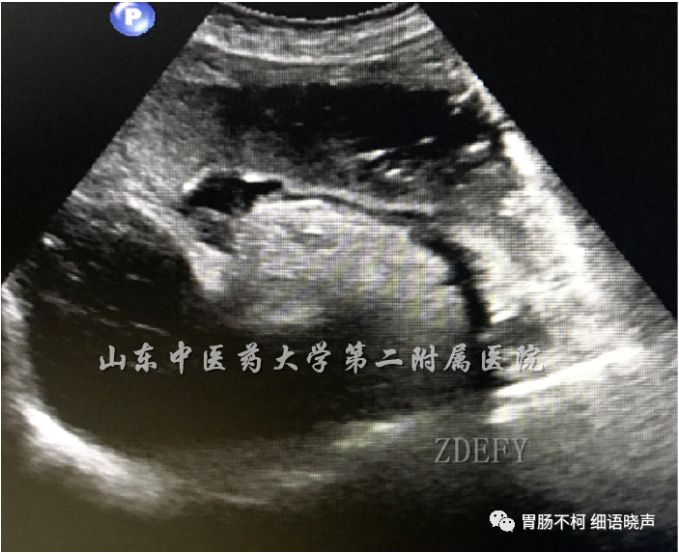

病例二:十二指肠球部见一低回声类圆形肿块

水充盈并放大图像后显示肿块近黏膜面可见黏膜表面上皮强回声线

CDFI:肿块周边及内部点、条状彩色血流信号

超声内镜显示腺体层来源特点

病理诊断:神经内分泌肿瘤G1